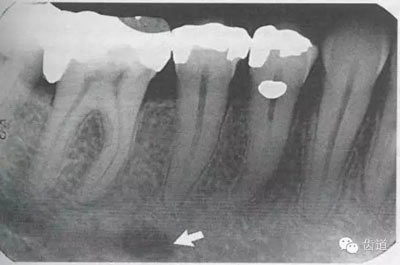

在投照上頜磨牙根尖片時,經(jīng)??梢钥吹窖栏戏接幸幻芏鹊偷挠跋?,為上頜竇的一部分,邊緣環(huán)繞以密度高的線狀影像,為上頜竇壁致密骨層。有時可見上頜竇的分隔。

可在第一、二磨牙根尖上方或重疊在牙根上為近似三角形或半圓形密度高的影像。

常在上頜第二、三磨牙的牙冠區(qū)域有一較牙密度稍低由后伸向前方的三角形影像。

4)外斜線:

由升支前緣下部斜向前下方,為一密度高的帶狀影像。常重疊在第二、三磨牙牙冠處、頸部或根部,使牙髓室或根管不能清晰顯示

5)下頜管:

位于磨牙牙根尖下方,呈寬約為0.4cm凹面向下邊緣整齊的帶狀密度低的影像,其兩側(cè)有密度高的線條狀影像,為下頜管骨密質(zhì)